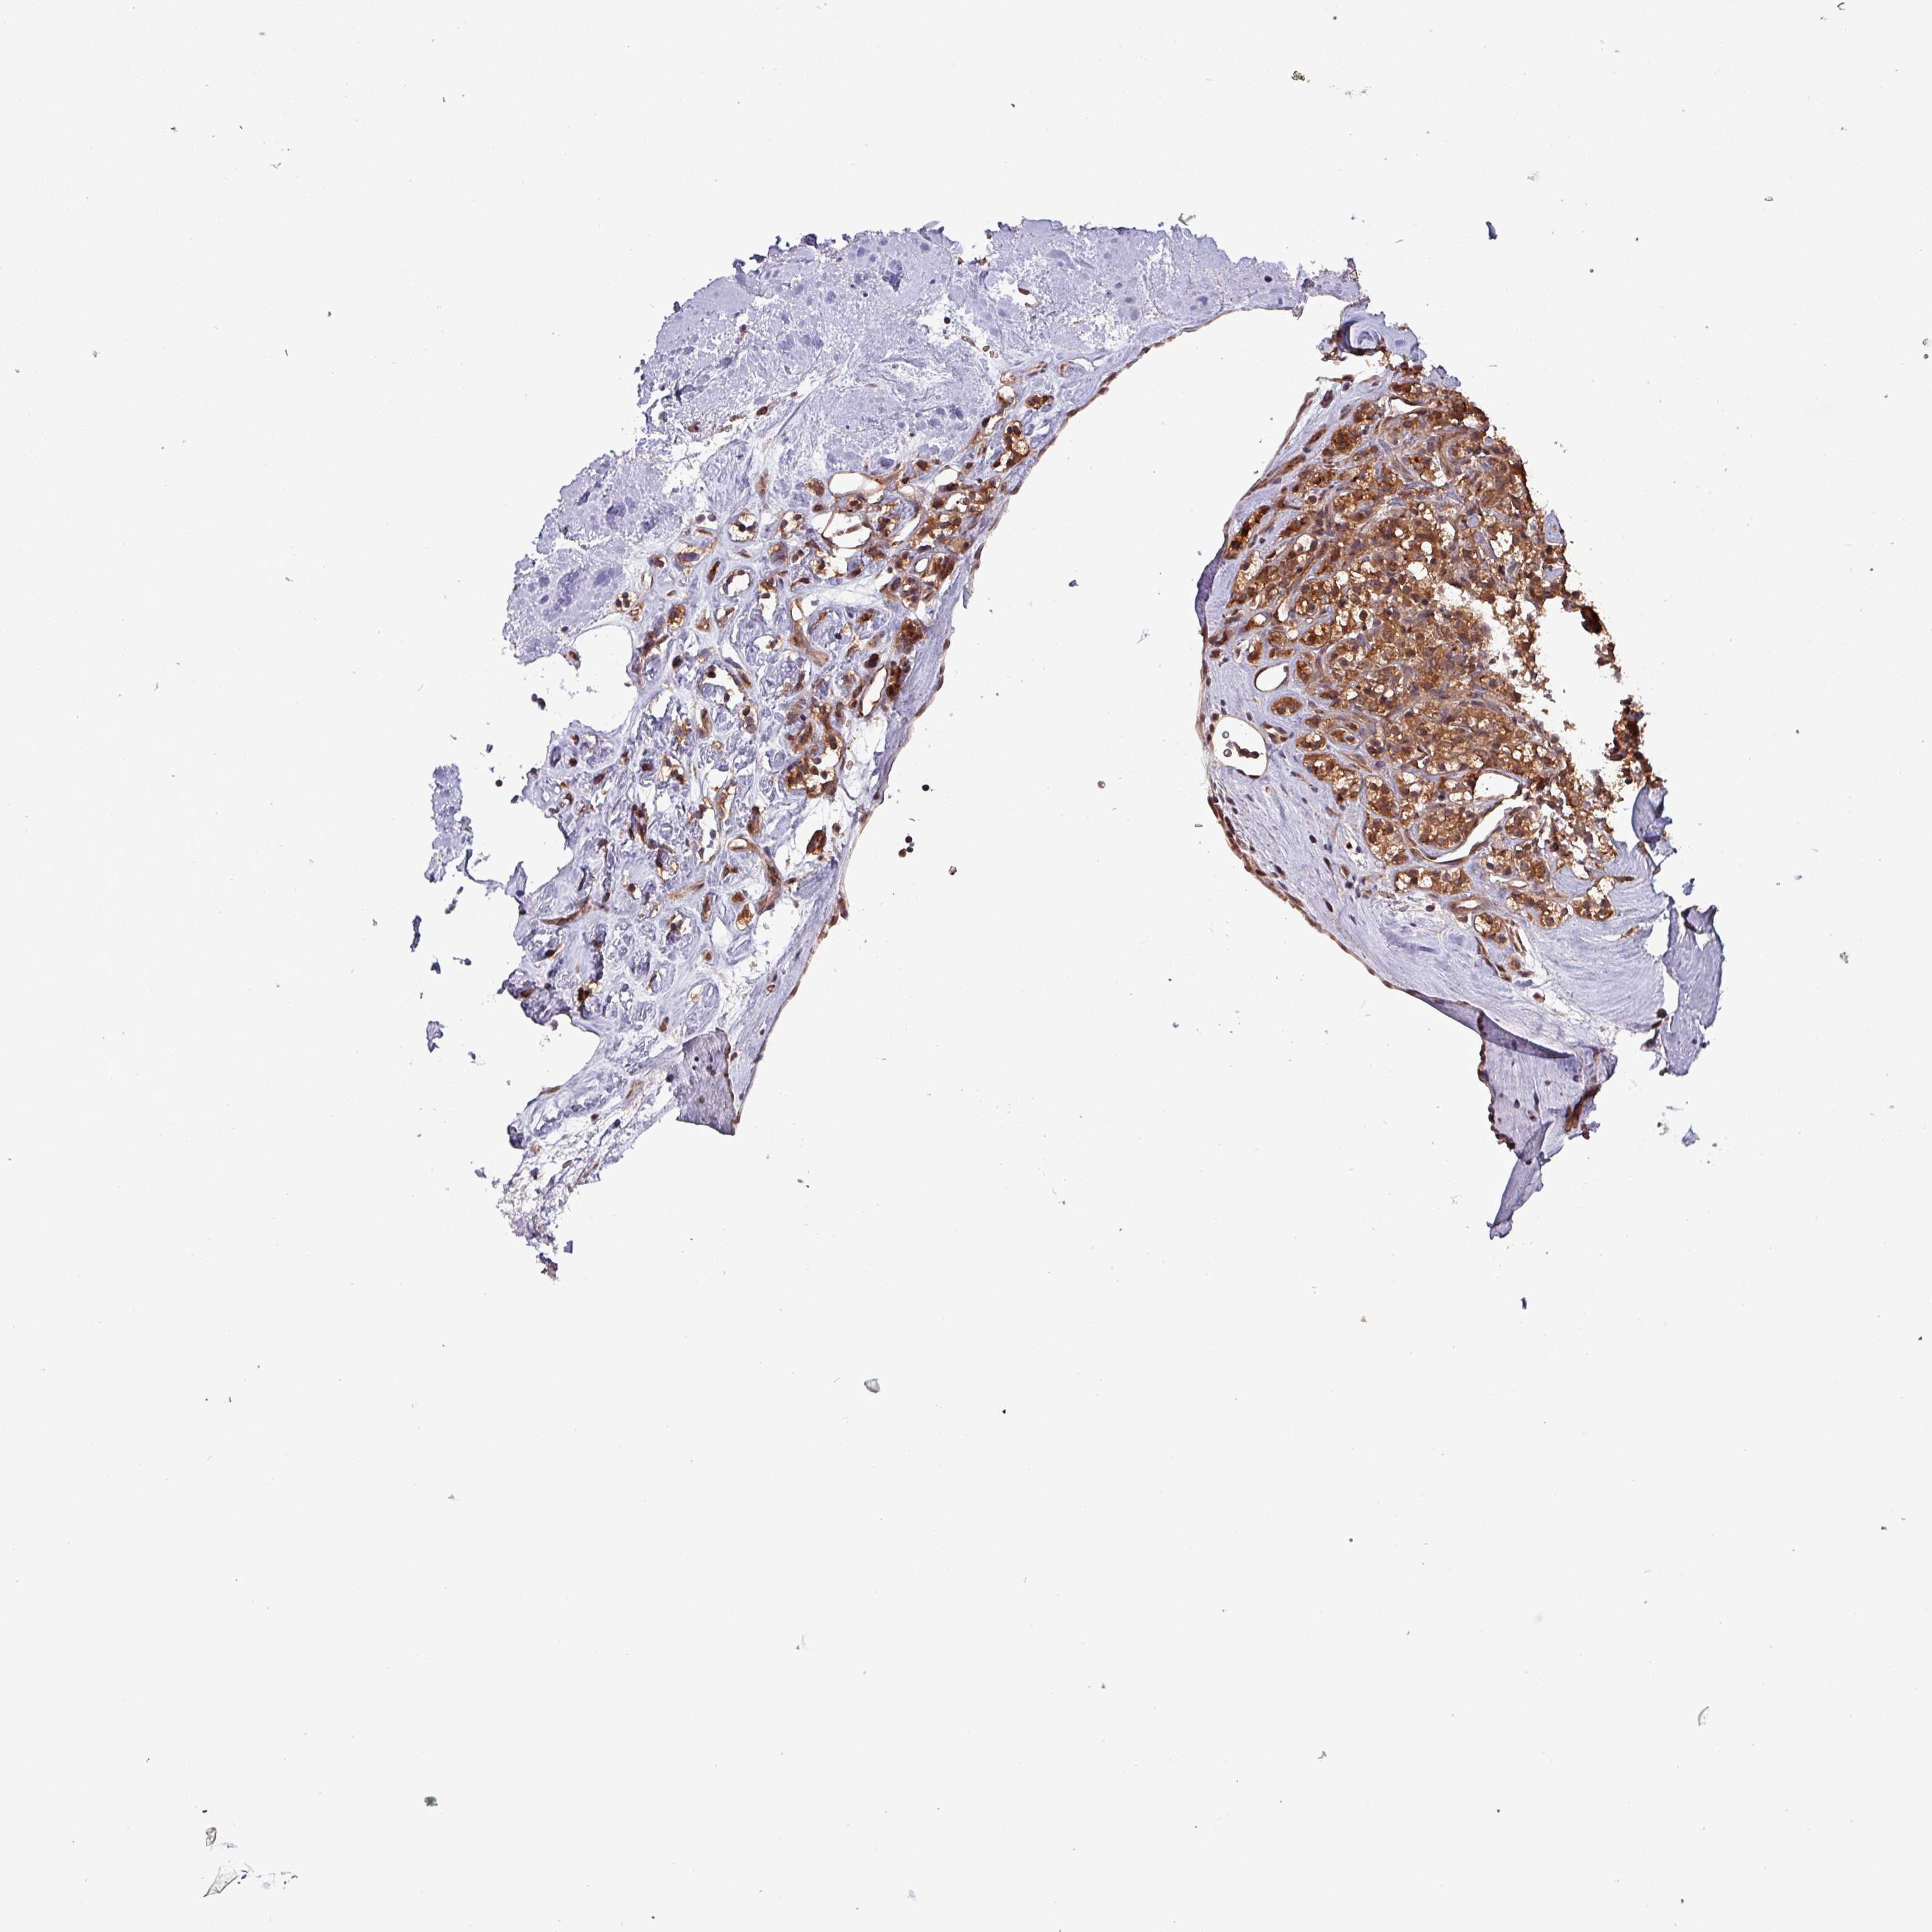

KIDNEY RENAL CLEAR CELL CARCINOMA (VALIDATION) - Interactive survival scatter ploti

The Survival Scatter plot shows the clinical status (i.e. dead or alive) for all individuals in the patient cohort, based on the same data that underlies the corresponding Kaplan-Meier plots. Patients that are alive at last time for follow-up are shown in blue and patients who have died during the study are shown in red.

The x-axis shows the expression levels (FPKM) of the investigated gene in the tumor tissue at the time of diagnosis. The y-axis shows the follow-up time after diagnosis (years). Both axes are complimented with kernel density curves demonstrating the data density over the axes. The top density plot shows the expression levels (FPKM) distribution among dead (red) and alive patients (blue). The right density plot shows the data density of the survived years of dead patients with high and low expression levels respectively, stratified using the cutoff indicated by the vertical dashed line through the Survival Scatter plot. This cutoff is automatically defined based on the FPKM cutoff that minimizes the p-score. The cutoff can be changed by dragging the vertical line or by entering a cutoff value in the square labeled "Current cut-off".

Under the Survival Scatter plot the p-score landscape (black curve; left axis) is shown together with dead median separation (red curve; right axis). Dead median separation is the difference in median mRNA expression between patients who have died with high and low expression, respectively. It is calculated as follows: median FPKM expression of dead patients with high expression - median FPKM expression of dead patients with low expression. This is intended to aid the user in visually exploring custom cutoffs and the associated p-scores and dead median separation.

Individual patient data is displayed and can be filtered by clicking on one or more of the category buttons on the top of the page. Categories describing expression level and patient information include: high, low, alive, dead, female, male and tumor stages. The scale of the x-axis can be toggled between linear and log-scale by clicking on the "x log" button. Mouse-over function shows TCGA ID, patient information and mRNA expression (FPKM) for each patient.

& Survival analysisi

Kaplan-Meier plots summarize results from analysis of correlation between mRNA expression level and patient survival. Patients were divided based on level of expression into one of the two groups "low" (under cut off) or "high" (over cut off). X-axis shows time for survival (years) and y-axis shows the probability of survival, where 1.0 corresponds to 100 percent.

PSMB8 is not prognostic in Kidney Renal Clear Cell Carcinoma (validation)

Best expression cut offi

Based on the FPKM value of each gene, patients were classified into two groups and association between prognosis (survival) and gene expression (FPKM) was examined. The best expression cut-off refers the FPKM value that yields maximal difference with regard to survival between the two groups at the lowest log-rank P-value. Best expression cut-off was selected based on survival analysis .

When clicking on this number, the vertical dashed line indicating cut-off, the interactive survival plot, and the Kaplan-Meier curve will be adjusted to show results based on the best expression cut-off.

: 16.63

Median expressioni

Median expression refers to the median FPKM value calculated based on the gene expression (FPKM) data from all patients in this dataset. When clicking on this number, the vertical dashed line indicating cut-off, the interactive survival plot, and the Kaplan-Meier curve will be adjusted to show results based on the median expression.

: N/A

Median follow up timei

Median follow up time refers to the median time (years) after diagnosis with this type of cancer, based on clinical data from all patients in this dataset.

P scorei

Log-rank P value for Kaplan-Meier plot showing results from analysis of correlation between mRNA expression level and patient survival.

N/A

5-year survival highi

5-year survival for patients with higher expression than the expression cutoff.

For melanoma and glioma, 3-year survival is shown.

5-year survival lowi

5-year survival for patients with lower expression than the expression cutoff.

TCGA RNA samplesi

RNA-seq data is reported as average FPKM (number Fragments Per Kilobase of exon per Million reads), generated by the The Cancer Genome Atlas (TCGA) .

Normal distribution across the dataset is visualized with box plots, shown as median and 25th and 75th percentiles. Points are displayed as outliers if they are above or below 1.5 times the interquartile range. FPKM values of the individual samples are presented next to the box plot.

Average pTPM 22.4

Number of samples 100